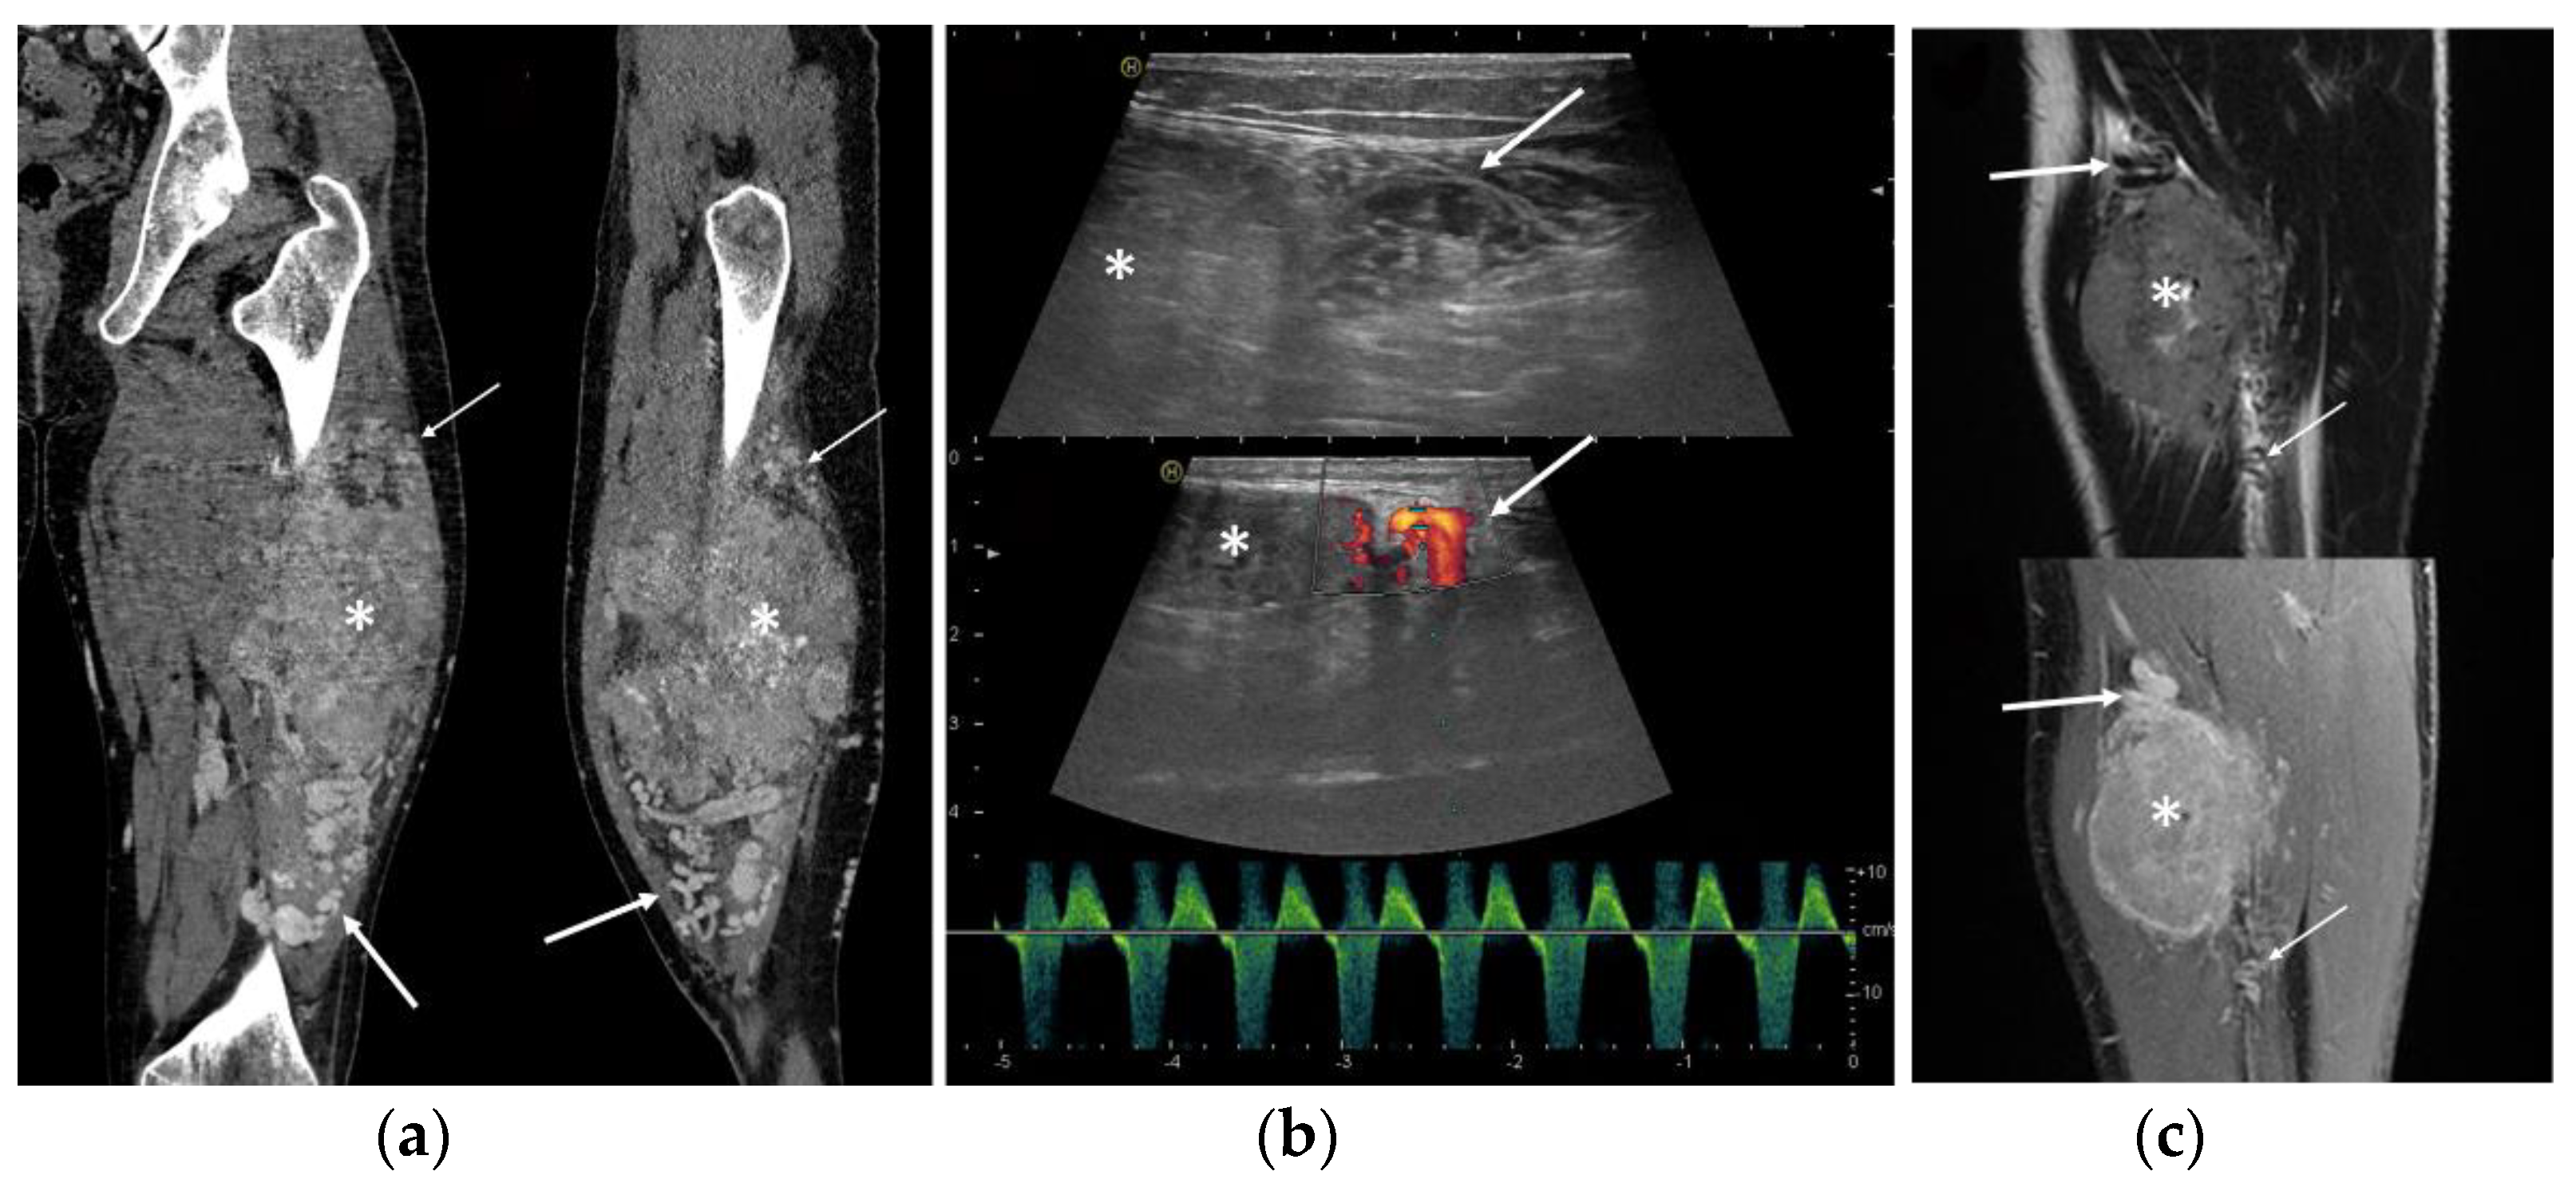

3.3. Ultrasound Features